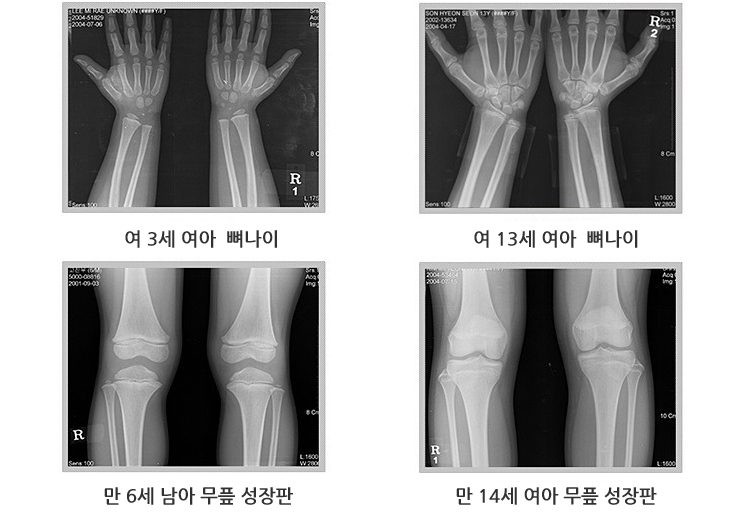

■ 골연령 측정

왼쪽 손목의 방사선 사진을 찍어 측정하며, 정상 표준과 대조해서 골연령을 판정합니다.

골연령 지연 여부에 따라 저신장의 원인을 감별할 수 있고, 성장판이 닫힌 경우라면 더 이상 성장은 일어날 수 없습니다.